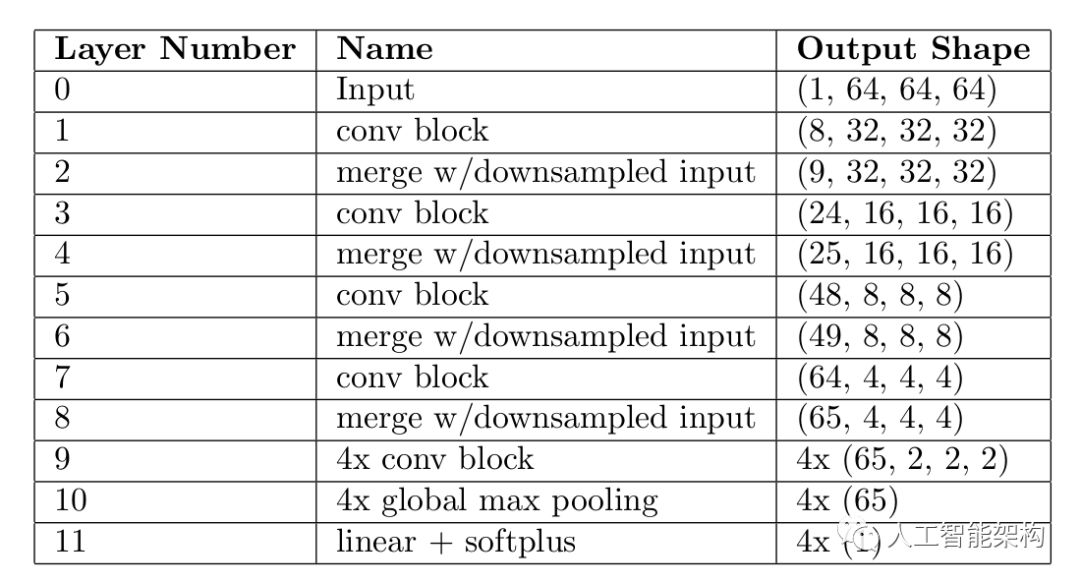

神经网络模型的输入数据为的CT,训练数据集包含了LUNA16的带注释的数据和LUNA16的假阳性数据。模型由5个卷积块(conv block)组成,以及全局最大池化层和带softplus激活函数的非负回归层。为了模型能在不同尺度上捕获信息,原始输入通过降采样(downsample)的方式输入至模型的每一层。由于模型的目标为非负的,因此使用softplus激活函数。3D卷积大小为

上表为重要结节属性的结构。其中,”4x“表示该层的4个并行副本,对于多输出模型中的每个输出都有一个副本。